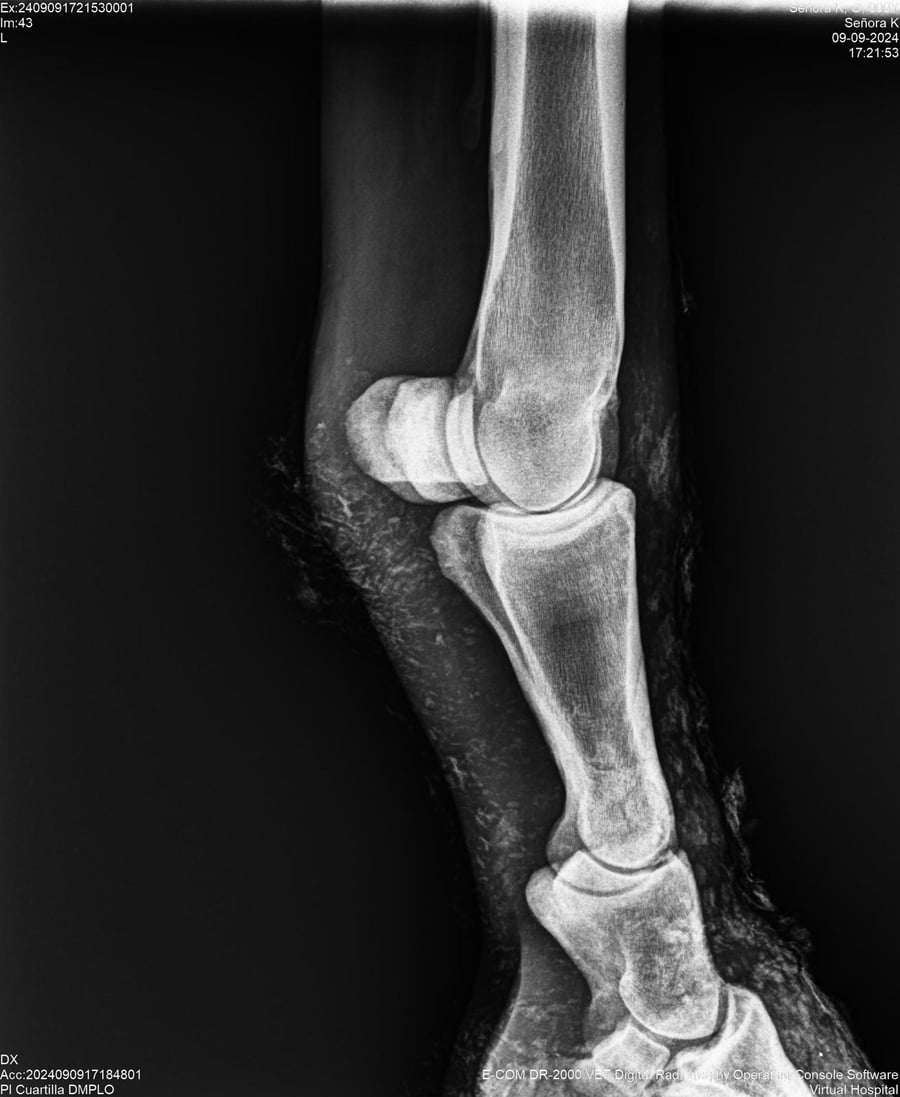

LOTE 44, SEÑORA K

Identificador: #291147-

Generacion 2022